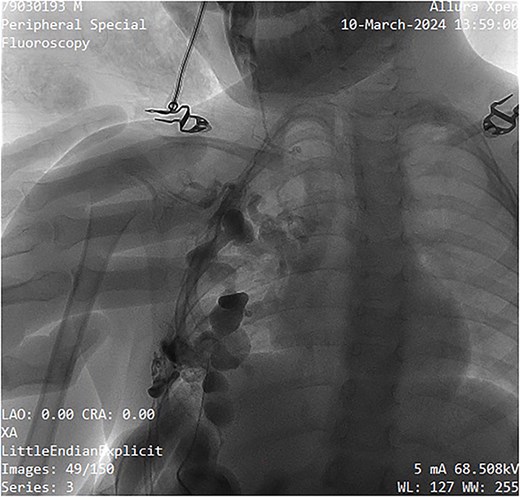

A single-needle direct-stick phlebography was performed using a 25-gauge butterfly cannula under ultrasound guidance. Blood aspiration confirmed the lesion's venous nature. Iopromide (Ultravist™) was administered and subsequent fluoroscopic imaging by Phillips Allura Xper FD System demonstrated slow contrast washout, further confirming the low-flow nature of the malformation (Fig. 3). Minimal venous drainage was observed, consistent with Puig Class I categorization [5].

Fluoroscopy image showing contrast administration into the malformation, confirming its slow-flow nature, and drainage pattern.